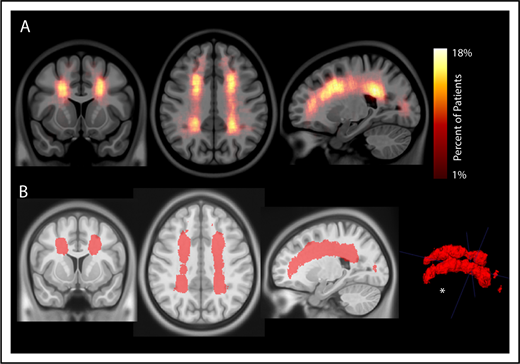

To evaluate the interaction between location and frequency of SCIs in pediatric SCA, an infarct density map from 286 participants with SCIs was created (Figure 2A). Infarct frequency within voxels ranged from 1 to 51 participants, and corresponding infarct density ranged from 1 to 18%. Infarct locations with the highest density were found in the white matter of the frontal and parietal lobes above and adjacent to the lateral ventricles.

Infarct density map from 286 children with SCA and SCIs in the SIT Trial. Infarct density was calculated for each voxel as the sum of participants with a lesion in that voxel divided by the total number of participants evaluated in the cohort. (A) Infarct densities range from 1% to 18%, with greatest densities falling in the deep white matter of the frontal and parietal lobes. (B) The infarct density map was thresholded to determine the region which encompassed SCIs from 90% of the cohort. The volume of this region was 5.6% of total intracranial volume. *SCIs for 90% of children are located within a confined region (5.6% of total brain volume).

To evaluate the spatial extent of SCIs encompassing most of the cohort, the infarct density map was thresholded to delineate the region capturing lesions from 90% of the population. SCIs from 90% of children were confined to a relatively small brain region measuring 5.6% of total brain volume (Figure 2B). The infarct density map was further analyzed for degree of symmetry between right and left hemispheres. Infarct densities for mirror voxels between the right and left hemispheres were highly symmetric (r = 0.878; P < .001; Figure 3). Most SCIs were located in white matter, with larger SCI volumes in white (median, 278 mm3; IQR, 125-772 mm3) compared with gray matter (median, 33 mm3; IQR, 3-146 mm3; P < .001). Children were most likely to have SCIs in the frontal lobes, followed by parietal, temporal, and occipital lobes (Table 2).

Silent cerebral infarcts in children with SCA are common, progressive, and associated with cognitive morbidity.4-8,31,32 We tested the hypothesis that the majority of SCIs would occur in the border zone region and the highest density of SCIs would occur in the region of lowest cerebral blood flow. In a large cohort of children with SCA and SCIs, we identified that the majority of SCIs were located within a common region in the deep white matter (Figure 2; Table 2). Further, by overlaying cerebral blood flow maps from an independent cohort of children with SCA, we demonstrated cerebral blood flow decreased as infarct density increased (Figure 4). These results are consistent with previous findings of stroke location in SCA showing that both SCIs fall within the white matter of the frontal and parietal lobes, and specifically within the border zone vascular distribution.4,18,33 Our findings are unique, in that we show 90% of children have SCIs within a relatively small border zone region, measuring 5.6% of total brain volume, and they occur in the region of low blood flow.